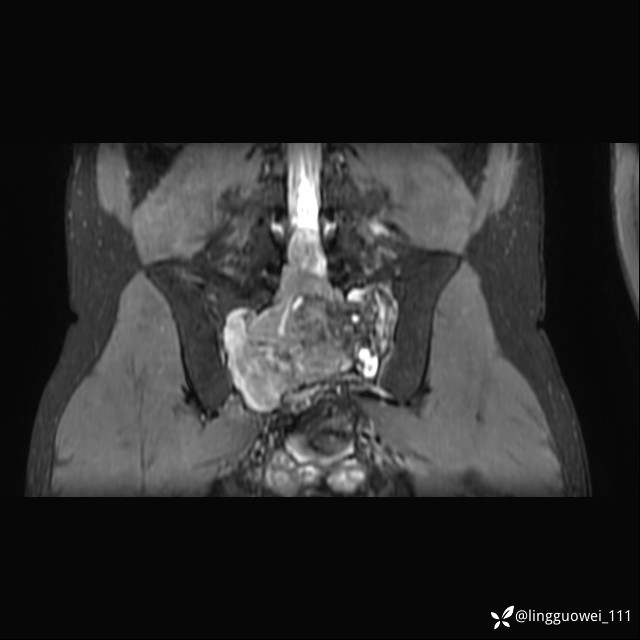

MR:(忘记截图常规序列,不过应该不影响诊断)

img